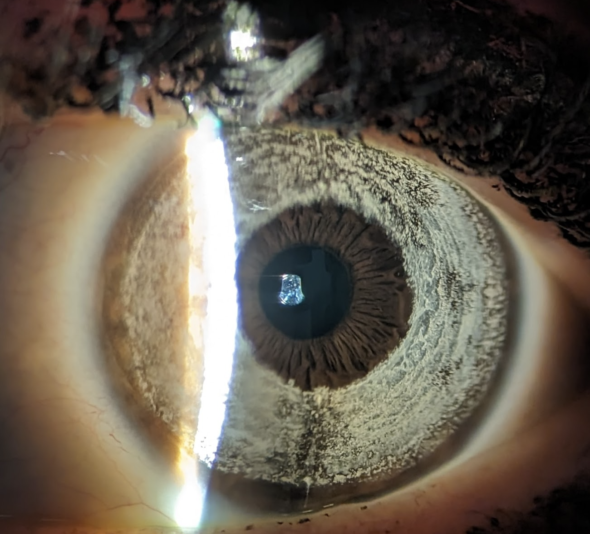

Prothèse d’iris artificiel destinées à changer la couleur d’yeux initialement marrons. A faible distance ou après grossissement, la texture et le motif diffère grandement de celui d’un iris naturellement bleu (implant « ice gray »). Ici, la prothèse est teintée en bleu (elle absorbe toutes les couleurs du spectre visible sauf le bleu), alors que les yeux qui sont naturellement bleus possèdent un iris peu pigmenté qui induit la diffusion accrue de la lumière bleue.

Aspect au biomicroscope; On visualise le chenal réalisé pour accérer au tunnel périphérique à 6h / 12h.